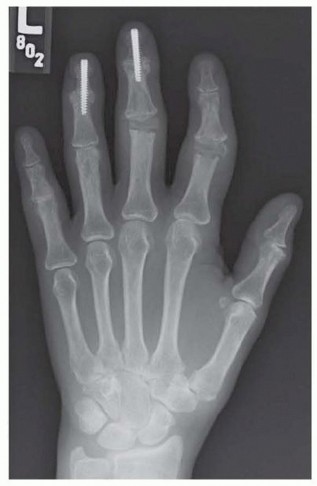

Radiographic evaluation begins with high-quality, orthogonal plain films (Anteroposterior, Lateral, and true Oblique views). These images are scrutinized for joint space narrowing, periarticular erosions, osteophyte formation, and the degree of subluxation.

FIG 1 • A. Rheumatoid arthritis affecting hand, with most notable disease affecting metacarpophalangeal (MCP) joints. The wrist is also affected.

FIG 1 • B. Isolated osteoarthritis of the MCP joint of the long finger.